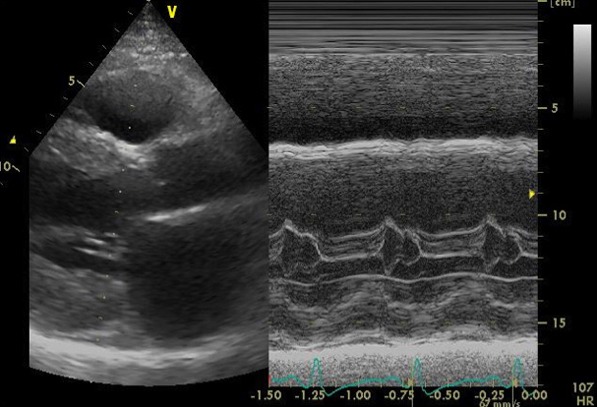

心エコー検査では、弁機能に異常なく、心嚢液の貯留はない。左房径(64mm)と左室径(60mm)は著明に拡張、左室は瀰漫性に壁運動の低下(EF=20%)。左室壁は中隔厚(18mm )、左室後壁厚(21mm)と共に肥厚しており、長年の左室圧負荷に加え、左室の収縮不全を認めることから、高血圧性心疾患に加え何らかの心筋疾患の可能性も否定できない。

心エコー画像1

心エコー画像2

心エコー画像3